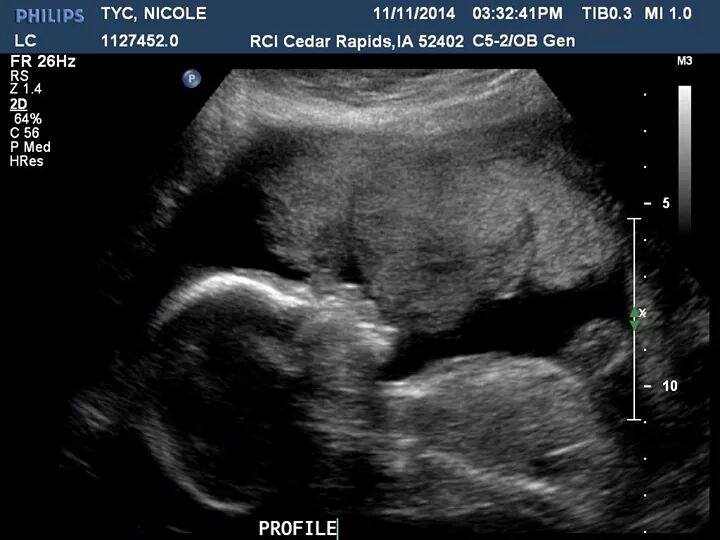

В январе 2013 года, сразу после встречи нового года, муж понял, что готов к ребеночку, чему я несказанно обрадовалась, так как я об этом мечтала давно, наверное даже всегда)) сколько себя помню, еще будучи маленькой девочкой, я мечтала как я вырасту и нарожаю много много детей, никогда не понимала девушек, которые не хотят детей. Понятное дело разные жизненные обстоятельства и тому подобное, но как не хотеть детей я не знала, это было моей какой-то целью) Ужасно завидовала в хорошем смысле подругам-мамочкам. Беременность у меня уже была, 6 апреля 2010 года я узнала, что беременна, тогда же нашла ББ, зарегистрировалась, 26 апреля 2010 года моя беременность закончилась...писать об этом не хочу, удалила тогда весь дневник и зашла на ББ только через полгода, а то и позже. Но это оставило на мне отпечаток, так как я фаталист, и считаю, что дети даются свыше и у них уже есть душа (может и бред, не спорю), но я молилась, чтоб ко мне вернулся мой сын (я была уверена, что тогда должен был быть мальчик). Это я к тому, что когда у нас с мужем не получилось в январе и феврале, я не расстраивалась, я думала, что все идет к повторению той ситуации и Бог дает мне второй шанс, но март пролет...в апреле я немного тушуюсь, так как был пост перед Пасхой, и тоже радовалась пролету, боялась я беременности в пост. Овуляция в мае выпадала на Пасху (примерно, плюс минус), но и тут пролет - приехала подружка в гости)) Надеялась, что получится после ПА перед овуляцией, что живчики доживут - не дожили... В июне я уже решаюсь на фолликулометрию, так как уже немного начинаю раздражаться от этого томительного ожидания перед днем Х уже в течение полугода, думаю, что проблема только в днях, что мы просто не попадали в овуляцию...и вот, счастливый день настает, узист сообщает, что вот вот случится чудо чудное диво дивное, я мужа в охапку, запомнила этот волнительный процесс